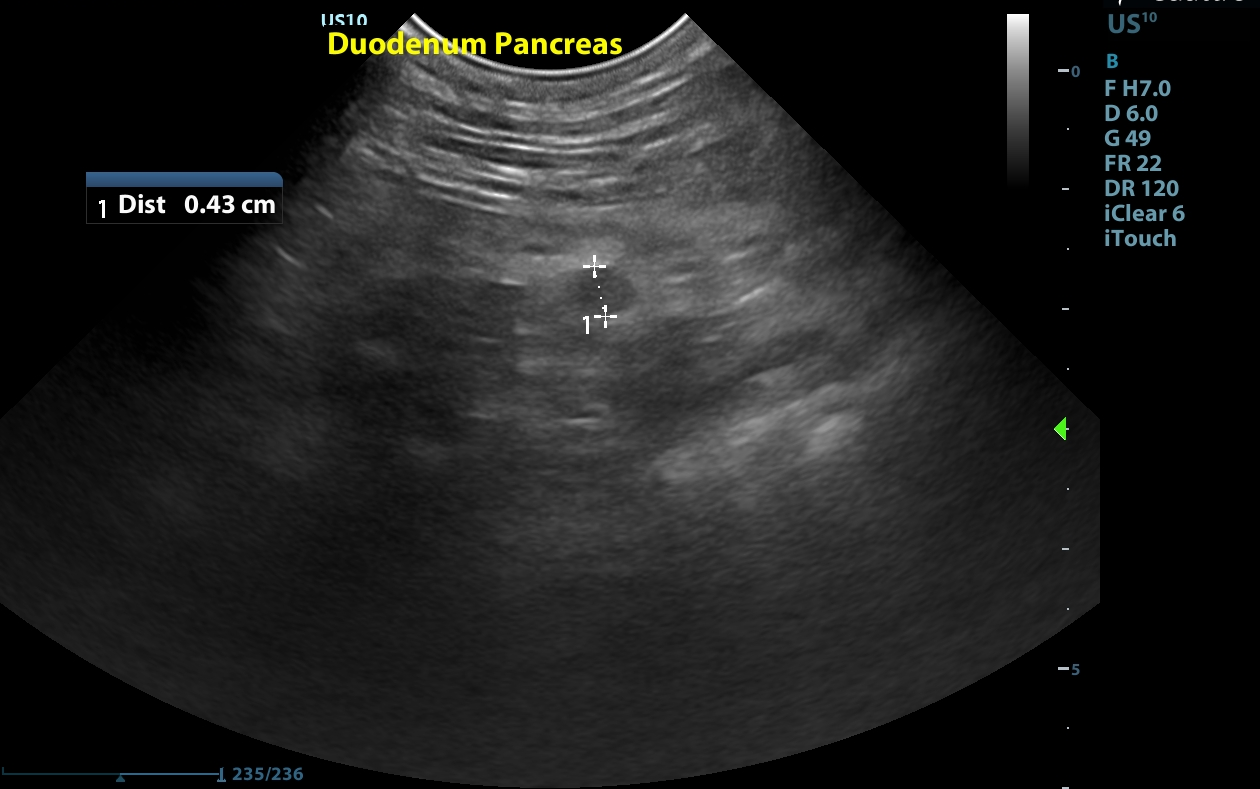

Serosal surfaces: The mesentery is diffusely hyperechoic and nodular particularly in the cranial abdomen where ill-defined hypoechoic small nodules are noted in the area of the pancreas. There is a small amount of echogenic peritoneal fluid noted in the caudal abdomen.

Mesentery - the findings are moderate - DDx: metastasis (e.g. carcinomatosis, lymphomatosis vs sarcomatosis) vs peritonitis - inflammation vs. paraneoplastic reaction vs. infectious vs. fibrosis vs. other.

Image 3: A small hypoechoic nodule noted near the pancreas.